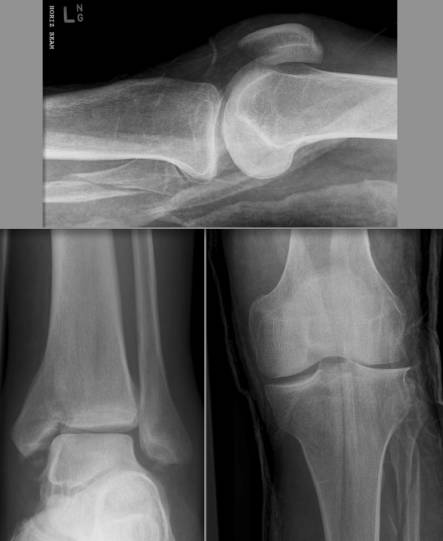

股骨髁的冠状位骨折,为关节内骨折。属于AO分型的B3型。

Segond骨折

胫骨平台前外侧撕脱骨折,多因为下肢过度内翻加内旋暴力所致,常伴有前交叉韧带、内外侧半月板的损伤。

反Segond骨折

胫骨平台内侧撕脱骨折,常因为下肢外翻应力加外旋所致。

Maisonneuve骨折

由外旋暴力导致的腓骨近端骨折, 常常合并下胫腓分离、内踝骨折、三角韧带撕裂、前距腓韧带断裂、骨间韧带损伤、下胫腓韧带撕裂、后踝骨折等损伤,属于旋前-外旋三度损伤,踝关节不稳定。